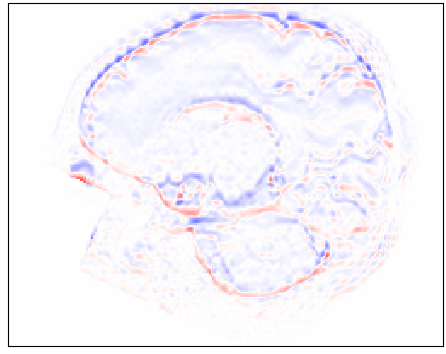

Slice Reconstruction: Results for reconstructed and synthesized slices listed in Table I convey that the proposed approach achieved high reconstruction performance especially in terms of SSIM and PSNR. Figure 4 depicts qualitative results of reconstruction performance for the proposed method on cardiac MRI. The results show that the trained autoencoder can reconstruct high-quality images i.e. input slices. Nevertheless, difference image shown in Figure 4(c) depicts that some high spatial frequency details of the input slice are lacking in the reconstructed slice.

Refer to caption

(a)

(b)

(c)

Figure 4: Qualitative evaluation of reconstruction performance of our method on cardiac cine MRI (ACDC dataset). (a) Original cardiac MRI scan; (b) Its reconstruction and (c) Differences between original (minuend) and corresponding reconstructed (subtrahend) slice. Note that to reconstruct a slice xnsubscript𝑥𝑛x_{n} the mixing coefficient α𝛼\alpha in Equation 1 is set to zero. Blue corresponds to negative and red to positive differences. Image intensities are scaled to a [0,1]01[0,1] range. All difference images use the same color scale [1,1]11[-1,1].